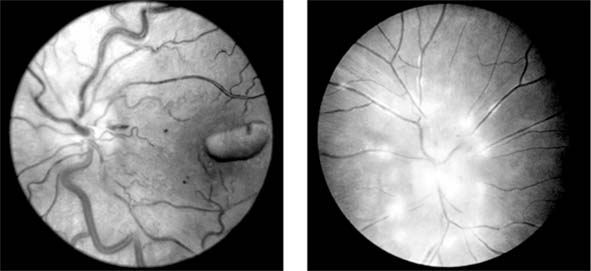

The ocular changes of leukemia occur primarily in those structures with a good blood supply, including the retina, the choroid, and the optic disk (Figure 15-14). Changes are most common in the acute leukemias, where hemorrhages are seen in the nerve fiber and preretinal layers.

Figure 15-14

Figure 15-14: Left: Retinal changes in chronic myeloid leukemia, where dilated veins and hemorrhages may be seen. Right: In acute lymphoblastic leukemia, infiltration of the disk may be seen.